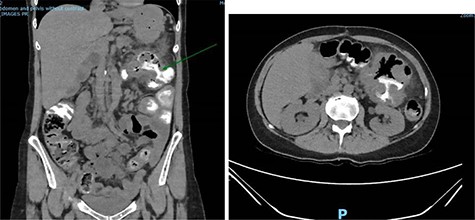

A repeat CT scan was performed, this time with oral contrast, which revealed a large gastrocolonic fistula into the transverse colon (Fig. 1). The patient underwent a gastroscopy and colonoscopy (Fig. 2A–C) which visually confirmed a 50 mm gastrocolonic fistula with a caliber sufficient to allow the passage of a colonoscope with relative ease (~13 mm), and no signs of active Crohn’s disease.

Coronal and axial slices of a CT abdomen/pelvis with oral contrast demonstrating a gastrocolonic fistula.